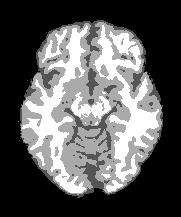

Magnetic Resonance Imaging (MRI) is a critical and widely used medical modality due to its noninvasive nature and ability to produce high-quality images of human organs and tissues. Segmentation in MRI refers to the process of dividing the acquired image data into specific tissues or regions of interest (ROIs). In the context of brain slice MRI data, this often involves distinguishing between cerebrospinal fluid (CSF), gray matter (GM), and white matter (WM), in 2D image slices as depicted in Fig. 1. Research topics on brain anatomy and functionality (e.g., Alzheimer’s disease, tumor detection, neurodegenerative processes, etc.) demand reliable segmentation tools since their outcomes directly impact the subsequent analysis of the brain slice MRI. Therefore, the development of any accurate MRI segmentation framework has to deal with the following issues:

(1) where can be interpreted as a smoother version of . With a little abuse of notation, we indicate the equation (1) as a cartoon-texture (CT) decomposition (even though we do not aim to compute a proper CT decomposition), where is the ‘cartoon’ depicting the structural component, and the ‘texture’ part including oscillatory components, like texture and noise, as shown in Figure 1.

Figure 3 illustrates the workflow of the algorithm SegMIC2T using the slice060 with low (top row) and moderate (bottom row) levels of the combined artifacts. The noise estimation step splits the original MRI slice into a cartoon image (second column) and a texture image (third column) (1). The correction step, coinciding with the application of the proposed multiaffine ADMM method, produces a denoised and debiased version of the original slice, whose th pixel corresponds to (fourth column). In the last step, the segmentation of the original slice is produced by clustering the pixels in the corrected image (fifth column).